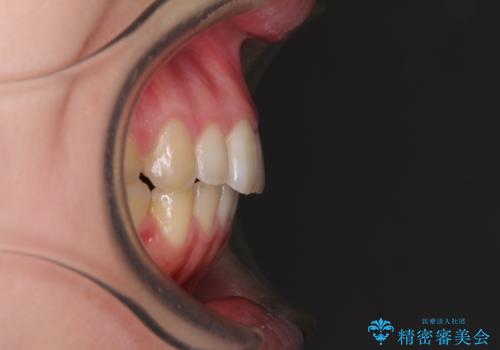

- 口の閉じにくさと割れてしまった奥歯を気にして来院された患者様です。

IPR(歯と歯の間を削る)と歯列全体の後方移動によって口元が引っ込むように設計し、インビザラインにより治療を行うこととしました。

割れてしまった奥歯は抜歯し、矯正治療中の良いタイミングでインプラントを埋入することとしました。

インプラントは、治療期間を短くすることが可能な、ストローマン社のSLActiveを使用することとしました。